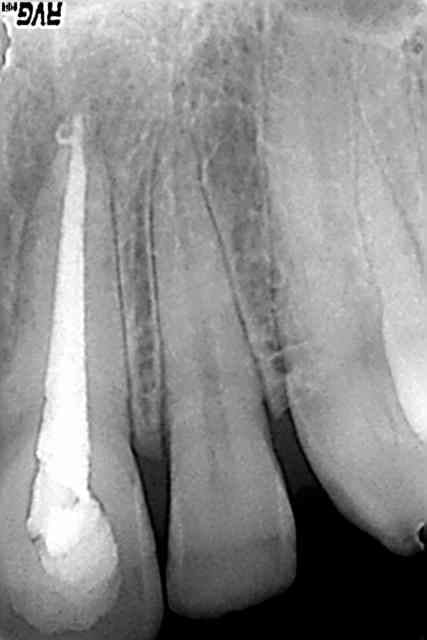

les 2 premières radios sont les pré op, puis 1 radio lime en place (je pensais avoir les 2 limes dans les 2 racines vestibulaires, mais en fait cette radio m'a permis de me rendre compte que je n'avais pas désobturé la distale), puis les 2 cones en place (on ne pouvait pas mettre les 2 cones en meme temps à cause de la constriction), puis obturation de la mésiale: j'ai coupé le cone pour qu'il ne sorte pas de la bifurcation, et j'ai poussé le bout, enduit de ciment, avec une sonde/le reste du cone de gutta, puis pris une radio pour voir dans quel canal le morceau était allé; mis les cones de gutta en conséquence, pris une radio, puis thermocompacté... puis radio post op...